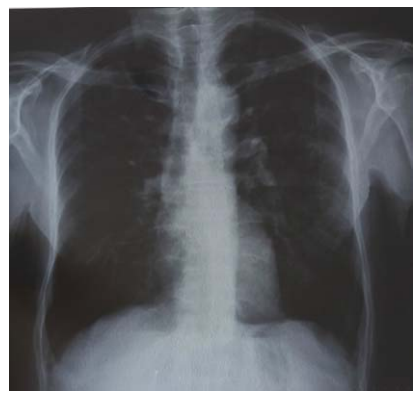

A las tres semanas regresa el paciente y es recibido el rayo x de tórax con lesiones sugestivas de proceso inflamatorio intersticial (Figura 1) y refiere el paciente continúa con dolor en miembros inferiores, que ha ido aumentando y 6 días atrás apareció dolor en región lumbar y cervical. Tratado con levofloxacino 500 mg una dosis por día, Loratadina 10 mg diarios y Prednisona oral, todo por 10 días. Se realiza rayo x columna cervical y lumbar mostrando signos de espondiloartrosis.